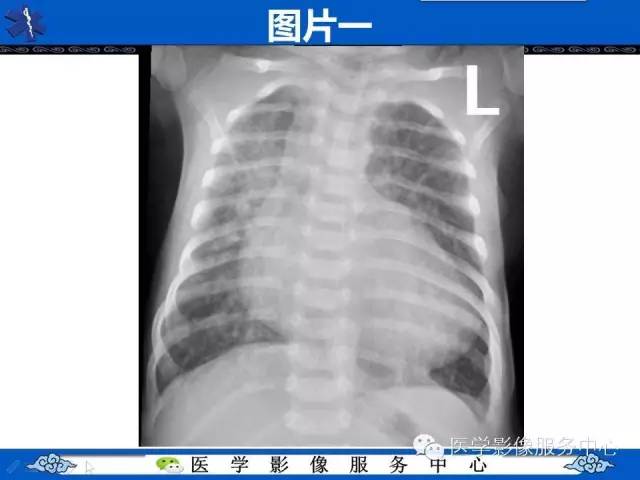

【影像征象】鸡蛋挂线征——大动脉转位征